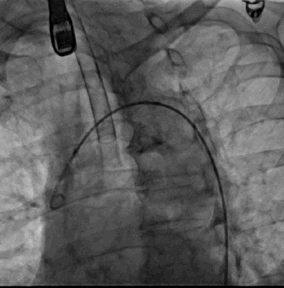

1. 患者于全麻下行LAAO术,常规消毒铺巾,经右桡动脉置入6F Sheath,右侧股静脉置入6F Sheath,左股动脉置入5F Sheath,5F pigtail后行主动脉弓造影

2. 经右桡动脉置入Sentinel CPS系统,释放于头臂干、左颈总动脉位